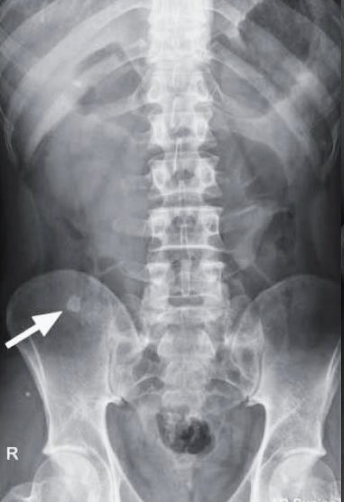

A

Fecalito